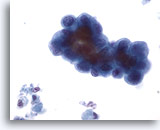

Figure 43

Voided urine, low grade carcinoma

Low grade urothelial carcinoma is characterized by increased clusters of cells. 20x

Figure 43

Voided urine, low grade carcinoma

Low grade urothelial carcinoma is characterized by increased clusters of cells.

20x

Voided urine, low grade carcinoma

Low grade urothelial carcinoma is characterized by increased clusters of cells.

20x